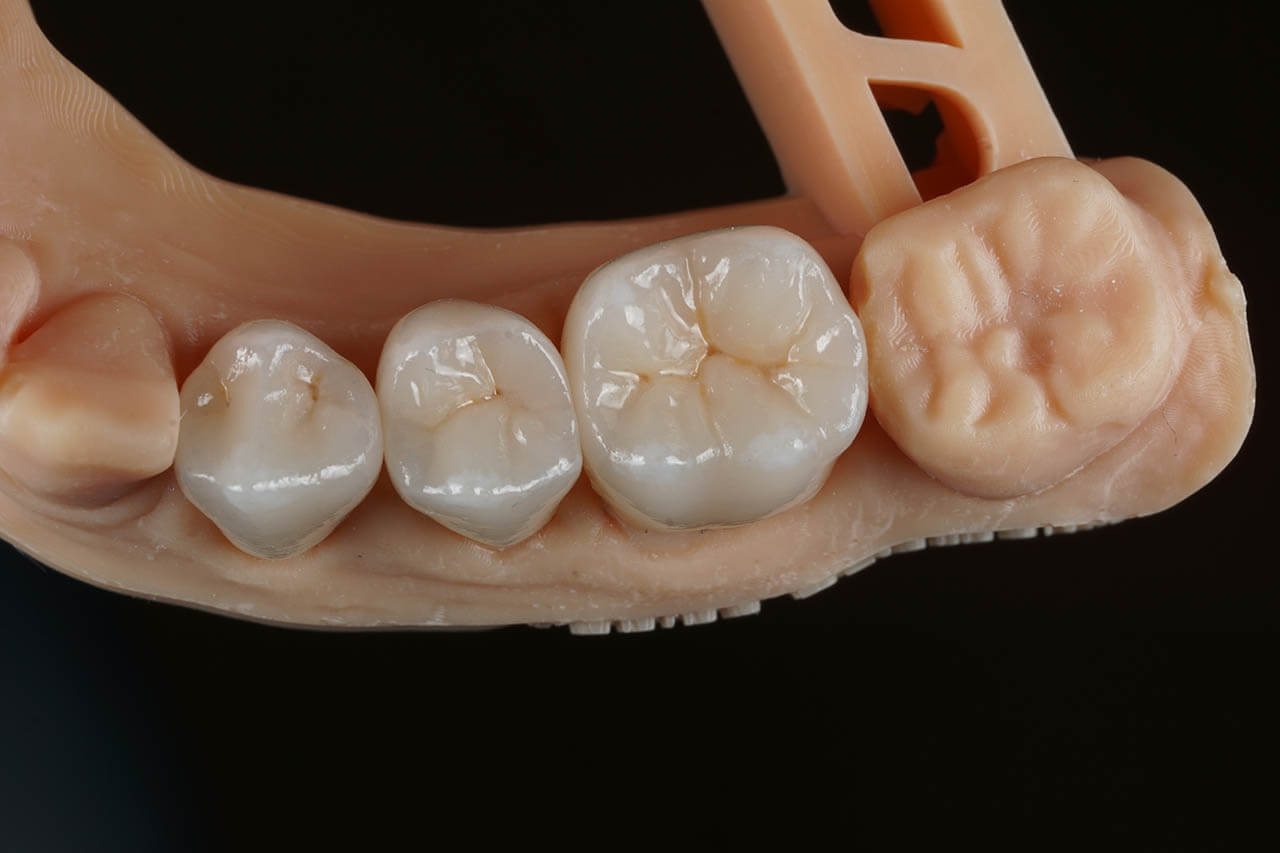

Dental prosthetics deals with filling gaps in the dentition and reconstructing damaged teeth. It is a good choice for anyone who in the past did not properly care for their teeth and as a result could not maintain their natural dentition or lost teeth due to illness or an unfortunate event. A properly chosen partial or full denture allows for the recovery of an aesthetic smile, good well-being, and self-confidence. Prosthetics at the Z Wieży clinic in Władysławowo offers you a wide range of modern prosthetic solutions, from which everyone can choose something tailored to their needs and expectations regarding the final result. Our experienced, highly qualified doctors are ready to provide assistance and good advice. To ensure the highest quality and aesthetics of restorations, we have for years cooperated with a renowned prosthetic laboratory.

Types of prosthetic restorations used at the Z Wieży clinic:

• Porcelain and all-ceramic prosthetic crowns;

• Acrylic and zirconia crowns;

• Dental bridges and dentures.

Our prosthetic work